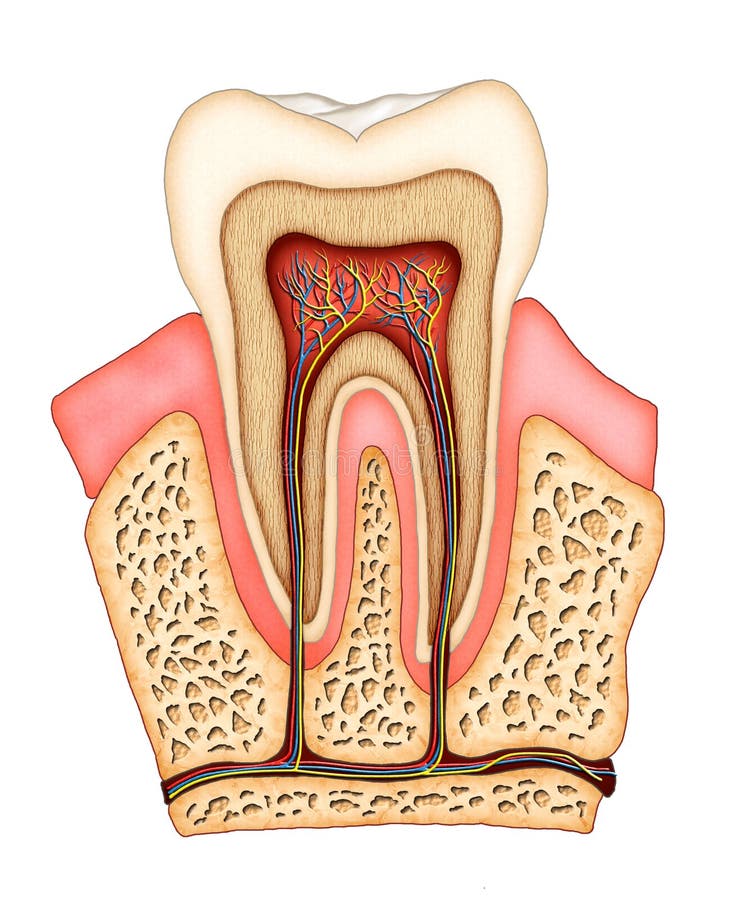

Tanden strukturerar Medicinskt diagram av strukturen av det inre tvärsnittet av tanden